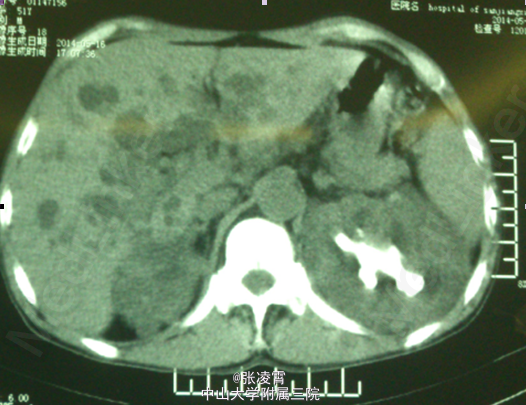

患者男性,51岁,因“左侧腰部胀痛不适20天余”入院。患者20余天前无明显诱因出现左侧腰部胀痛,未伴有发热,寒战,恶心,呕吐,轻度尿频,尿急,尿痛等不适,至柳州市工人医院就诊,尿蛋白+2g/L,潜血阳性,WBC(++),血红蛋白69g/L,肌酐450umol/L;KUB示双肾多发结石,双肾ECT示左肾GFR21.09ml/min,右肾8.84ml/min,考虑为双肾多发结石伴左肾及肾周感染,慢性肾功能不全,尿路感染,肾性贫血,经抗炎等对症治疗后,症状有所缓解。 实验室检查:尿常规:白细胞计数98http://www.medlinker.net/m/casem/12628336计数12.3个/μL,血常规:血红蛋白计数:64g/L。血生化:碳酸氢盐12.0mmol/L,肌酐443μmol/L。凝血四项未见明显异常。 影像学检查:KUB示:双肾多发结石,左侧为著,部分为铸型结石(图1)。外院CTU示:多囊肾,多囊肝,双肾结石(图2、3)。